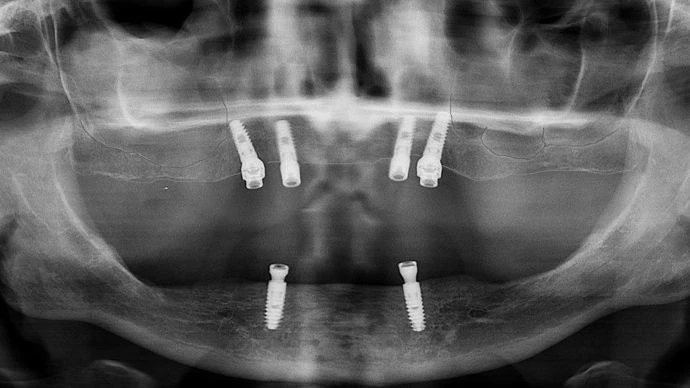

С четири мини импланта може да се проведе лечение предимно в долна челюст. Цялата зъбна протеза е поставена върху 4 неостеоинтегрирани мини импланта. Мини имплантите са едночастови с дебелина 1,8 – 2.0 мм.

/горна челюст – 4 зъбни импланта/

/долна челюст – 2 зъбни импланта/